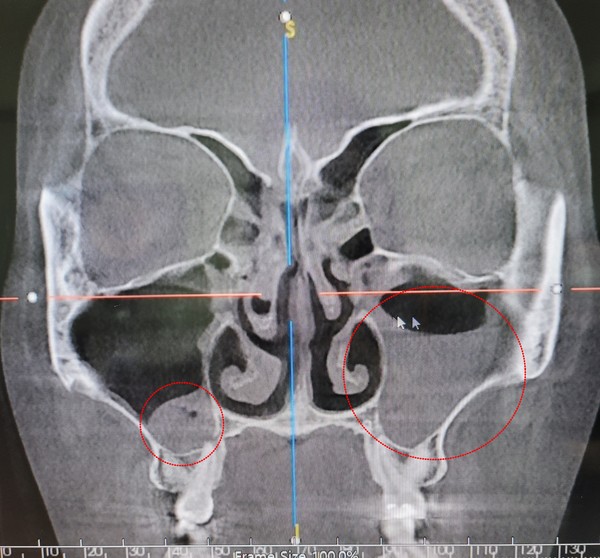

2020년 11월엔 비중격만곡증으로 코 성형 수술을 받았다. 수술 후 일주일이 지난 시점부터 아이코스를 피우기 시작했다. 그러자 얼굴이 무거워지는 느낌과 함께 진한 녹색 콧물과 가래가 나왔고 진료 결과 축농증 진단을 받았다.